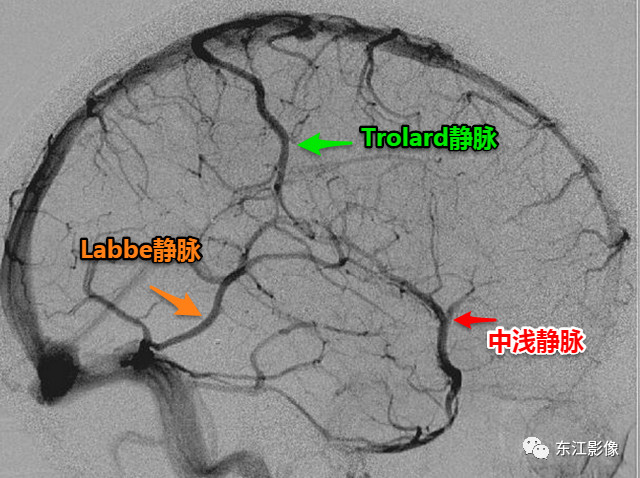

4)大脑浅静脉

大脑表浅静脉可分为上、中、下三组。因为这些静脉变化不一,多无具体名称。但有三大支皮层静脉常可认出,但同时出现的概率并不大。

正常的表浅静脉变异相当大。

图6 大脑中浅静脉是一明显而不恒定的静脉或一组静脉,沿侧裂表面走行。

收集(引流)侧裂及脑岛盖区的数小属支。

大脑中浅静脉旋即向前围绕颞叶尖端并向内走入海绵窦或蝶顶窦。

大脑中浅静脉常见多发,如有脑裂畸形或皮层发育不良等先天畸形,覆盖于畸形脑上的静脉也往往异常。

Trolard静脉是主要的上吻合静脉,又名额顶静脉,是一支大而不恒定的血管,它从侧裂后上行,走到大脑半球中部凸面。连接大脑中浅静脉与上矢状窦。

Labbe静脉是下吻合静脉,又名枕颞静脉。此静脉沿枕颞沟在颞叶上走,连接大脑中浅静脉与横窦。

在75%解剖标本中此静脉可见于一侧或两侧大脑半球。